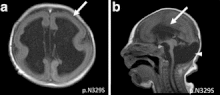

.gif)